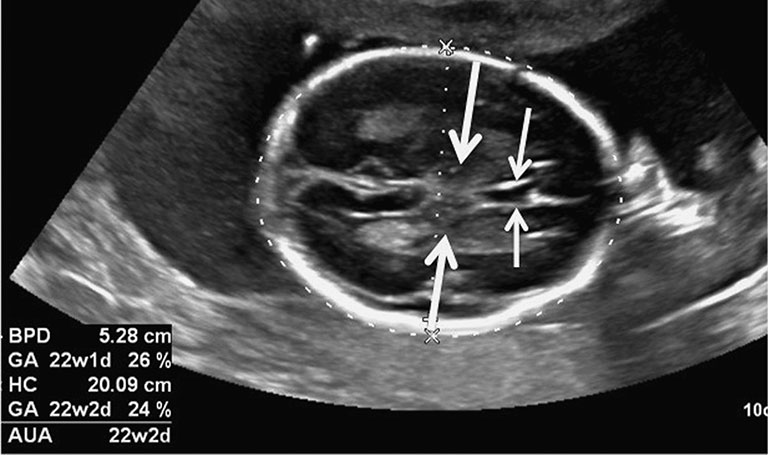

Chỉ số BPD (Biparietal Diameter) trong siêu âm là đường kính lưỡng đỉnh, được đo từ mặt cắt lớn của trán đến phía sau gáy của thai nhi. Có thể coi chỉ số này như đường kính của đầu bé. Nhiều người có thể nhầm lẫn giữa chỉ số BPD và HC, nhưng thực tế hai chỉ số này hoàn toàn khác nhau. Trong khi BPD chỉ đo đường kính của đầu, HC là chu vi của đầu thai nhi.

Bác sĩ có thể bắt đầu đo đường kính lưỡng đỉnh BPD trong siêu âm từ tuần thứ 13 của thai kỳ. Dữ liệu này sẽ được ghi nhận liên tục trong các lần khám sau. Nhiều nghiên cứu cho rằng chỉ số BPD đạt độ chính xác cao nhất khi thực hiện trong khoảng từ tuần 13 đến 20, thời điểm mà đầu của thai nhi đang phát triển mạnh mẽ, thuận lợi cho việc đánh giá. Nếu đo chỉ số này khi thai lớn hơn, độ chính xác có thể bị giảm.

Chỉ số BPD trong siêu âm thai sau tuần thứ 12 cho đến hết thai kỳ rơi vào khoảng 88 - 100mm, trung bình là 94mm thì được cho là bình thường.